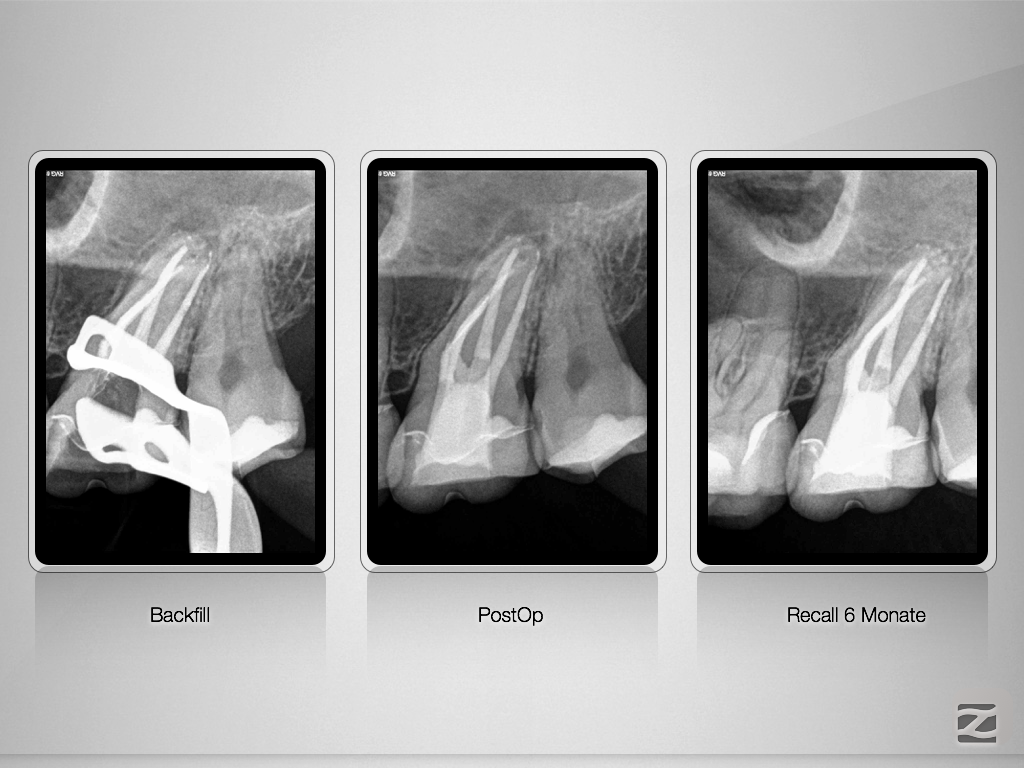

Vitales Gewebe – apikale Aufhellung